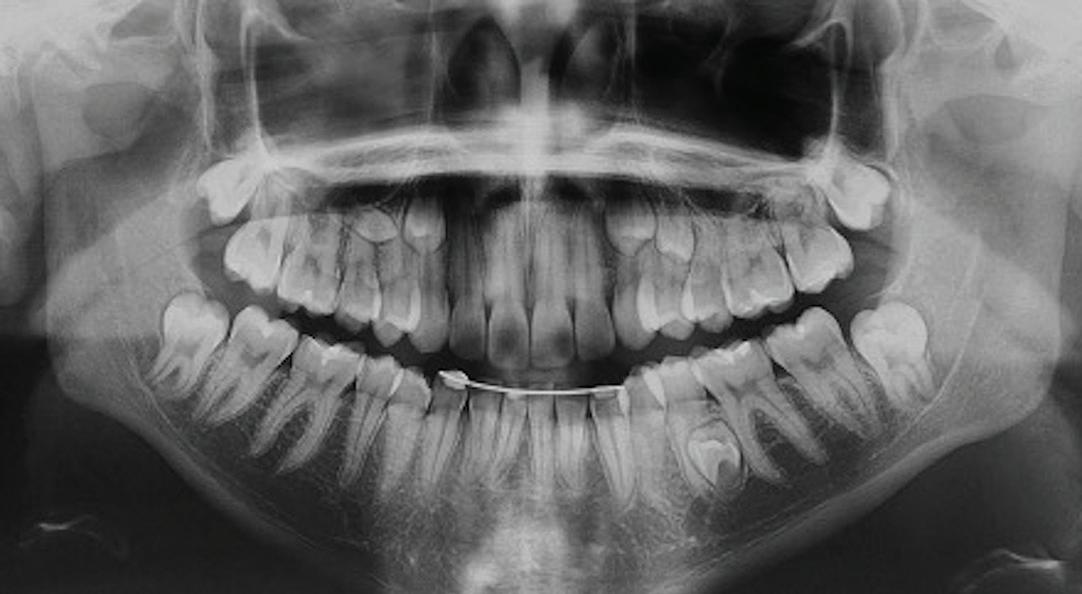

54 Oral and Maxillofacial Surgery

Root migration after coronectomy of impacted mandibular third molars: case reports